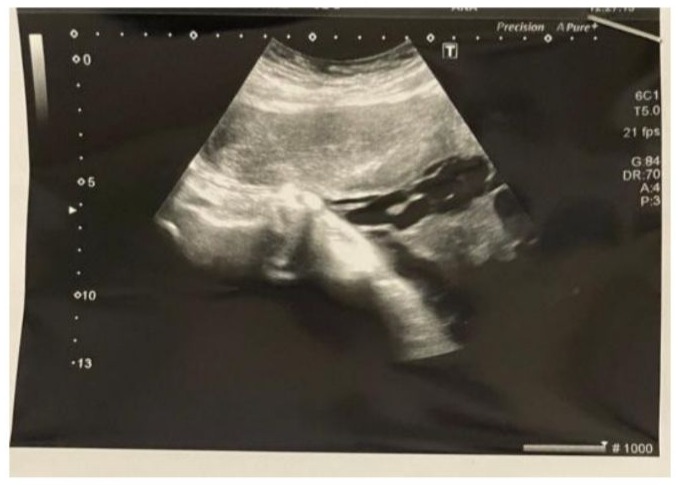

- Drainage of hematometra under general anaesthesia was performed through cervical dilatation under ultrasound guidance, due to worsening pelvic pressure symptoms and progressive distension seen on imaging. See pic [1,2]

Figure 2: Abdominal Ultrasound Post Drainage of Hematometra Showing Empty Uterus.